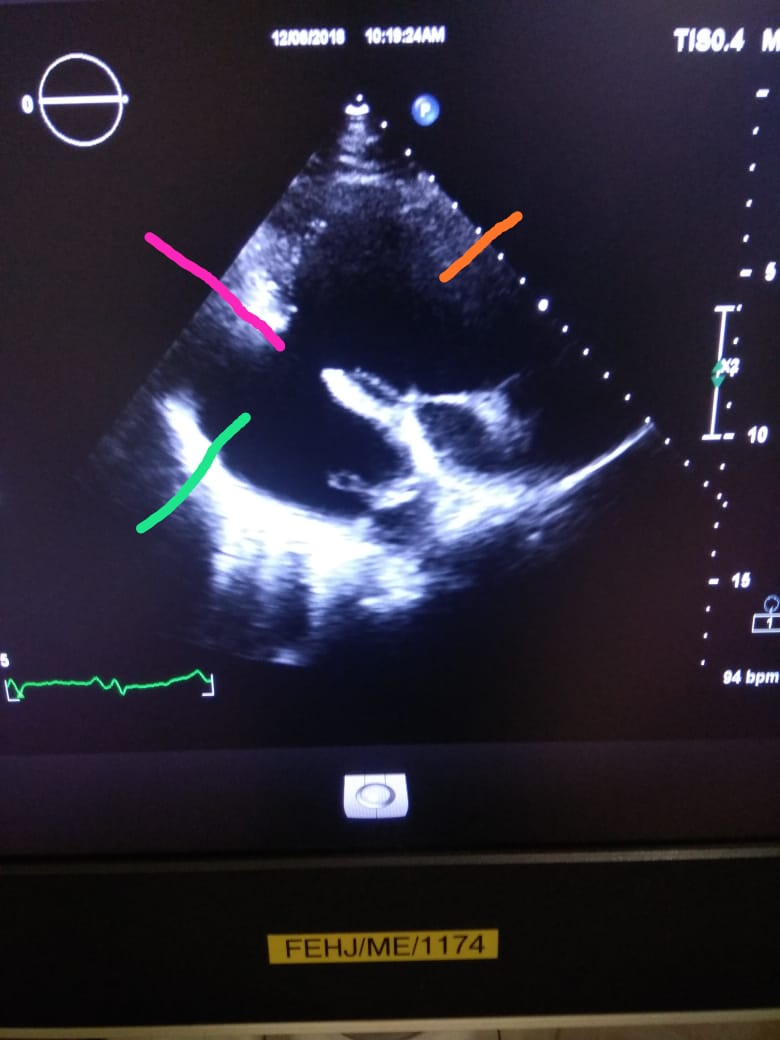

aortic bifurcation. On further investigation he was found to have CONTAINED RUPTURE OF LEFT

VENTRICLE WITH LARGE COMMUNICATING PSEUDOANEURYSM WITH CLOTS.